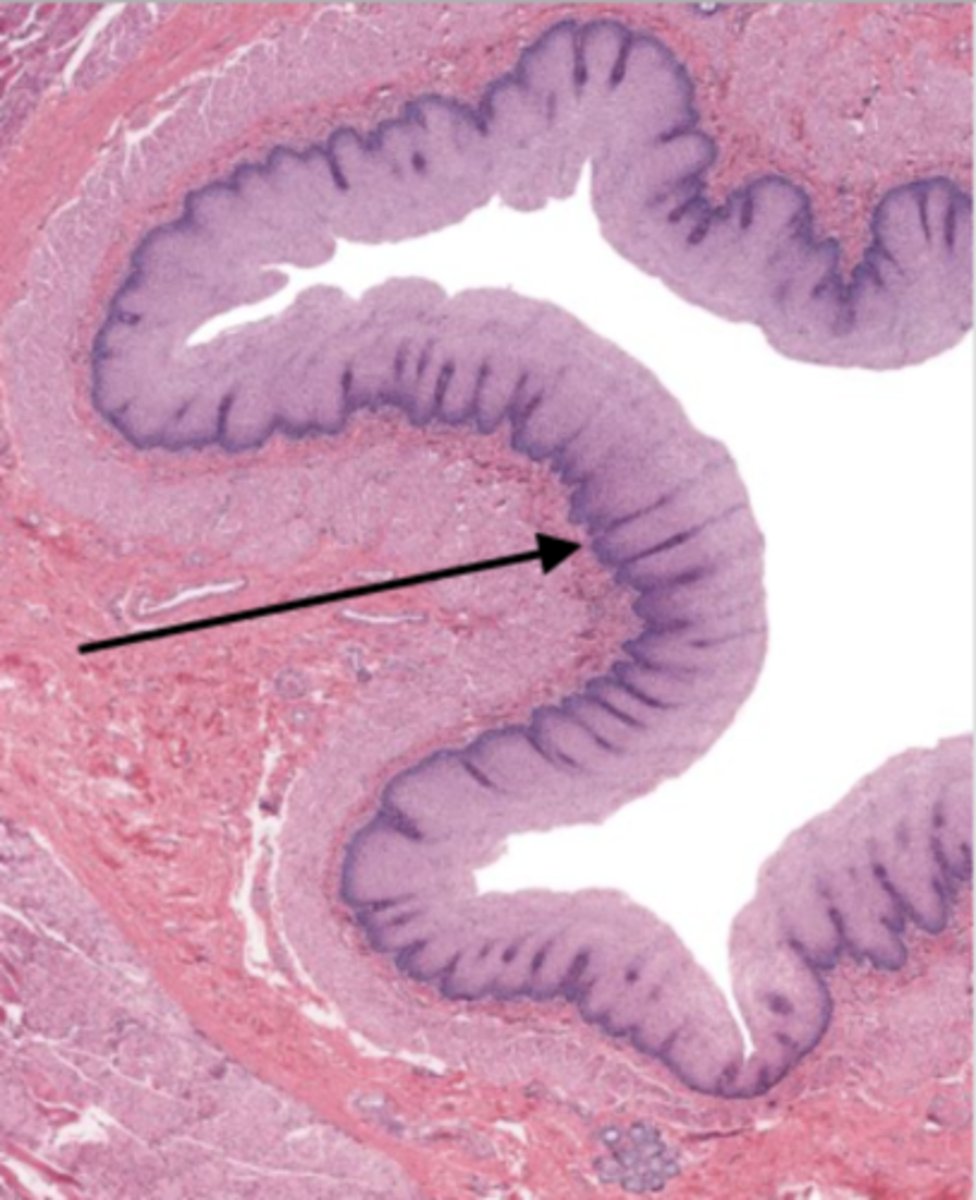

jejunum (histology)

villi (jejunum)

intestinal crypts (jejunum)

lumen (jejunum)

mucosa (jejunum)

mucosal epithelium (jejunum)

lamina propria (jejunum)

muscularis mucosa (jejunum)

submucosa (jejunum)

contains glands and blood supply

muscularis externa (jejunum)

serosa/adventitia (jejunum)